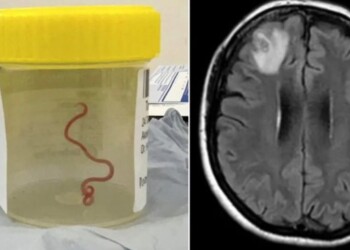

Descubren por primera vez en la historia un gusano parásito en el cerebro de una mujer

Una mujer australiana de 64 años padecía síntomas extraños desde hace mucho tiempo y los científicos descubrieron que se trata ...